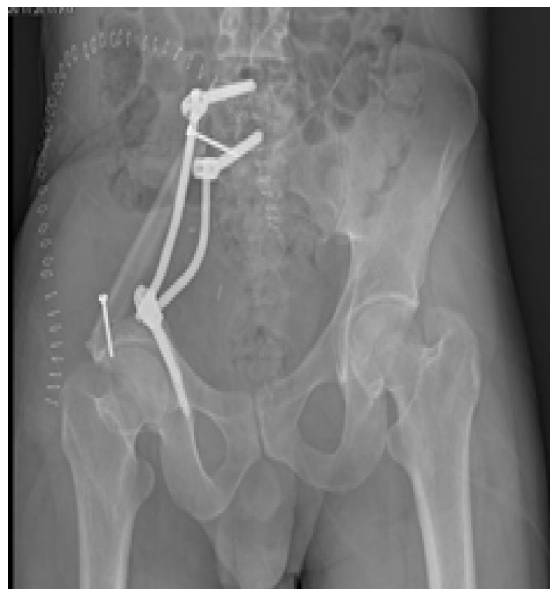

Ameliyat Sonrası: Röntgende sakroiliak rezeksiyon sonrası fibula ve pedikül vidası/rodlar ile rekonstrüksiyon görünmekte